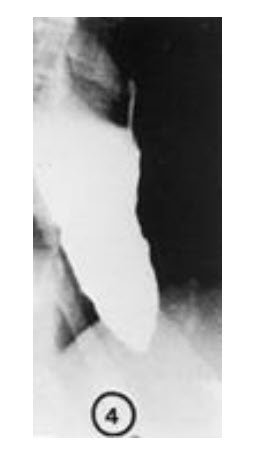

A 72-year-old woman notices progressive dysphagia to solids and liquids. There is no history of alcohol or tobacco use, and the patient takes no medications. She denies heartburn, but occasionally notices the regurgitation of undigested food from meals eaten several hours before. Her barium swallow is shown.

The barium swallow shows the dilated baglike proximal esophagus and tapered distal esophageal ring characteristic of achalasia. This is a motor disorder of the esophagus and classically produces dysphagia to both solids and liquids. Structural disorders such as cancer and stricture usually cause trouble swallowing solids as the first manifestation. In achalasia, manometry shows elevated pressure and poor relaxation of the lower esophageal sphincter. In classic achalasia the contractions of the esophagus are weak, although a variant called vigorous achalasia is associated with large-amplitude prolonged contractions. Medications (nitrates, calcium channel blockers, botox injections into the LES) or physical procedures (balloon dilatation or surgical myotomy) that decrease LES pressure are the recommended treatments. Squamous cell carcinoma would not cause esophageal dilation and would be associated with ratty rather than smooth tapering of the esophagus. Achalasia is not associated with gastroesophageal reflux disease. Although anxiety can cause dysphagia and a globus-like sensation in the cricoid region, it would not cause the anatomical changes seen on this barium swallow.